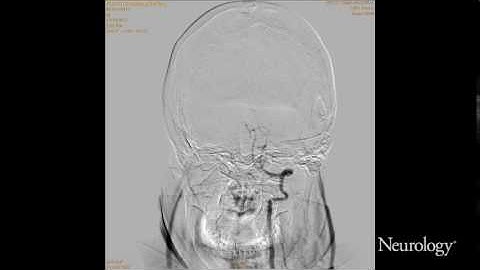

A Spontaneous Basilar Artery Dissection With an Intimal Flap Imaged With Several Techniques